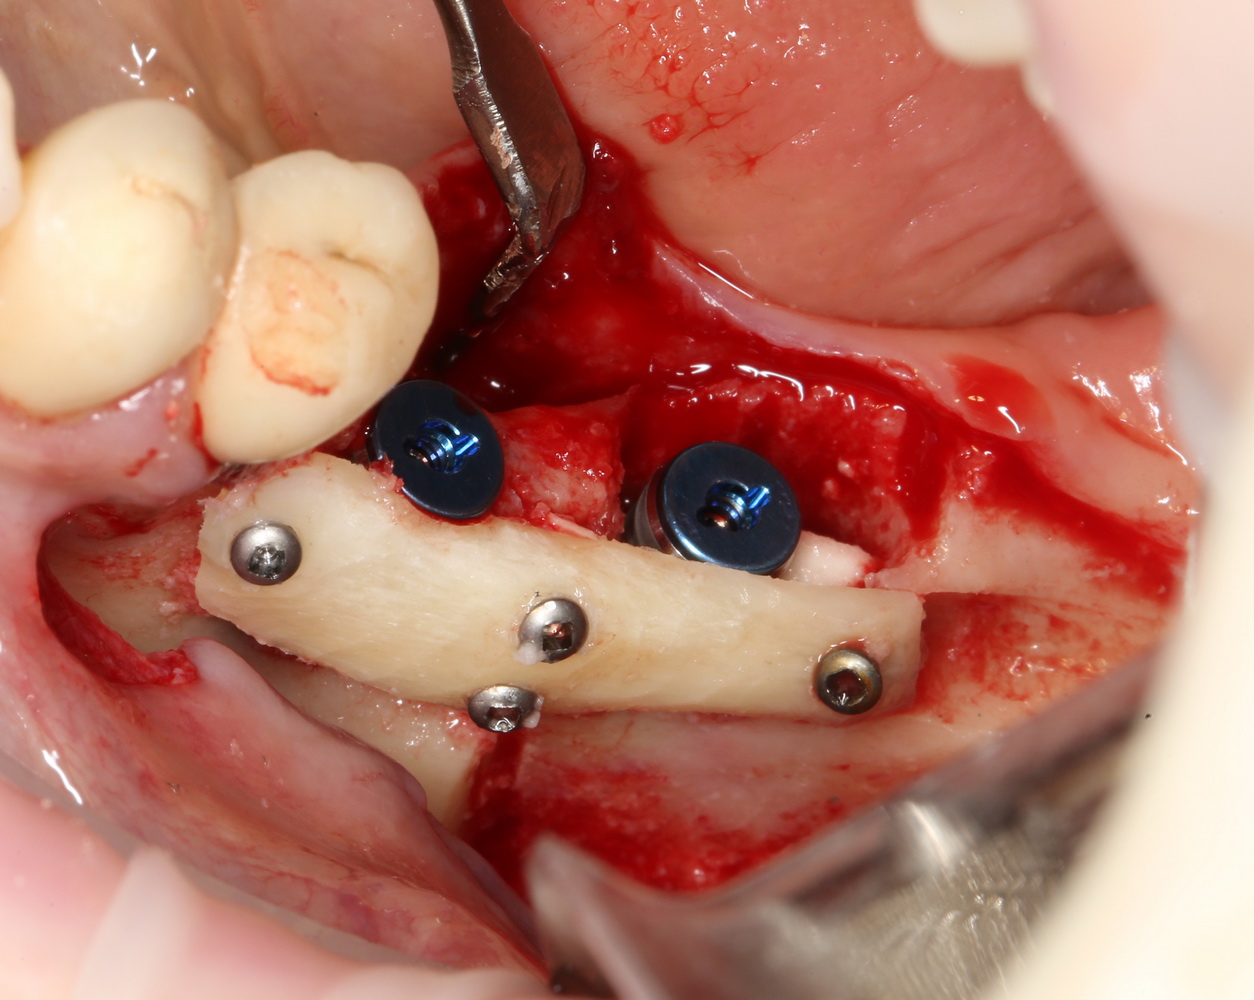

Несложная остеопластика в пределах 1-2 зубов занимает примерно столько же времени. При отработанном планировании и правильной подготовке, комбинированная остеопластика с от первого разреза до последнего шва вполне укладывается в 45-60 минут:

Не аппендэктомия за 7 минут, но все же…